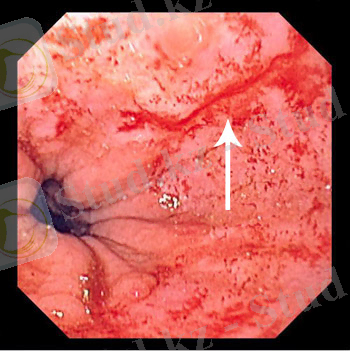

Мэллори-Вайс синдромын диагностикалаудың негізгі әдісі - эндоскопиялық тексеру, ол диагностикалық мақсаттан басқа, қан кетуді тоқтатуға бағытталған бірқатар манипуляциялар жасауға мүмкіндік береді. Зертханалық қан есебін зерттеу жағдайдың ауырлығын бағалауға көмектеседі.

Эндоскопиялық тексеру

ФГДС - өңештің жарылуын анықтау, қан кету және оның тоқтауы

ФГДС енгізу көбінесе науқастағы тоқтаған қанды одан ары ушықтыруы мүмкін(ФГДС-ке қарсы құсудың пайда болуы) .

ФГДС әсерінен жыртылған өңештің одан асқынуы

ФГДС вена арқылы наркоз жүргізу және құсуға қарсы препараттар енгізу арқылы жасалады

Эндоскопия сізге асқазан-ішек шырышты қабатының зақымдану орны мен сипатын анықтауға мүмкіндік береді.